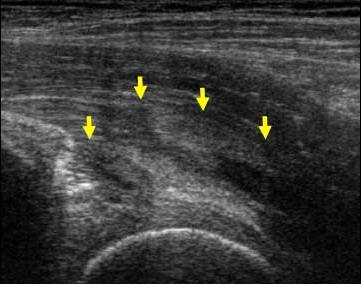

Stadiul III Rodineau – mica colectie lichidiana

Echivalentul stadiului al III-lea a lui Rodineau se caracterizeaza prin prezenta unei colectii hematice intra sau peri lezionale

Aceasta colectie poate avea o ecostructura lichida sau pseudo-solida, coresponzand unui hematom organizat

In acest caz, doppler-ul este interesant caci permite eliminarea unei formatiuni tisulare vascularizate care constituie principalul diagnostic diferential.